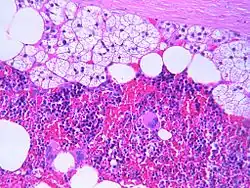

Pathologie

Myelolipome sind gelbe bis bräunliche, wenige Millimeter bis 30 cm große, umschriebene, jedoch nicht gekapselte Tumoren. Sie treten üblicherweise solitär und einseitig im Bereich einer Nebenniere auf, werden selten jedoch auch bilateral und/oder außerhalb der Nebenniere (z. B. im Retroperitoneum, Mediastinum, der Leber, in Muskelfaszien) gefunden. Mikroskopisch setzt sich der Tumor aus reifem Fettgewebe und myeloiden Zellen zusammen. Gelegentlich werden Infarktareale, Einblutungen oder knöcherne Metaplasien beobachtet.[1][2]